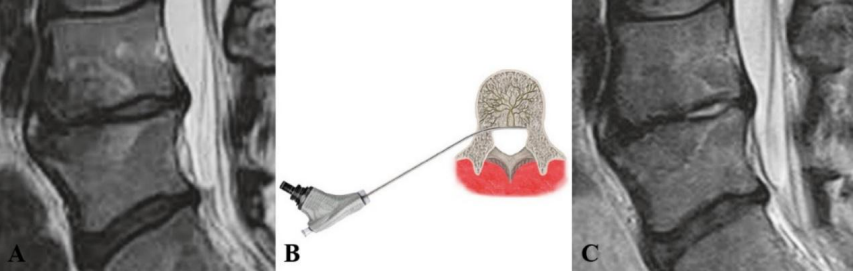

①吸收骨水泥的椎体增强术

a、b 和 c 提示 L4/5 椎体 Ⅰ 型 Modic 改变,d 提示 L4、L5 进行骨水泥注射的术中影像,e 提示术后复查 L4 椎体骨水泥填充情况。